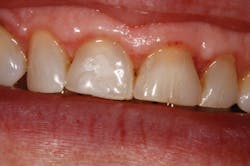

Figure 2: Immediate post-op

Figure 5: Complete with e.max crowns

The patient was anesthetized with 1 carpule of 4% articaine with epinephrine 1:100,000. The entire procedure was performed using Solea's "Hard and Soft Tissue" setting. Excess gingiva was removed using the Solea Ultraguide handpiece with a 600-micron tip, 14 mm length, and the 0.25 mm spot size. One percent mist and cutting speed between 20% and 40% were selected. The bone adjacent to the tooth was removed until the proper gingival architecture was achieved with the corresponding bony architecture 3 mm apical to the desired gingival margins. This was accomplished using the same Ultraguide tip, 0.25 mm spot size, 100% mist, and cutting speed between 40% and 60%. Full mist is always used with bone. A piezo scaler was used to smooth the root surface and remove any spicules of bone on cementum. The total procedure time was approximately 40 minutes (figure 2). The patient was reevaluated at seven days (figure 3) and 30 days (figure 4). Preparation and impressions for IPS e.max (Ivoclar Vivadent) crowns for teeth No. 8 and 9 were completed after three weeks, and final crowns were inserted (figure 5).

Solea's precision and ability to maintain a clean surgical site allowed this unscheduled procedure to be completed successfully. Additionally, rapid healing was observed (figure 3). With Solea, this was a minimally invasive procedure and crowns were prepared 30 days postoperatively (figure 5). Traditional surgery would require six to eight weeks until proper conditions were established for definitive restorative work. In addition, there would have been more postoperative pain and slower healing with traditional instruments.